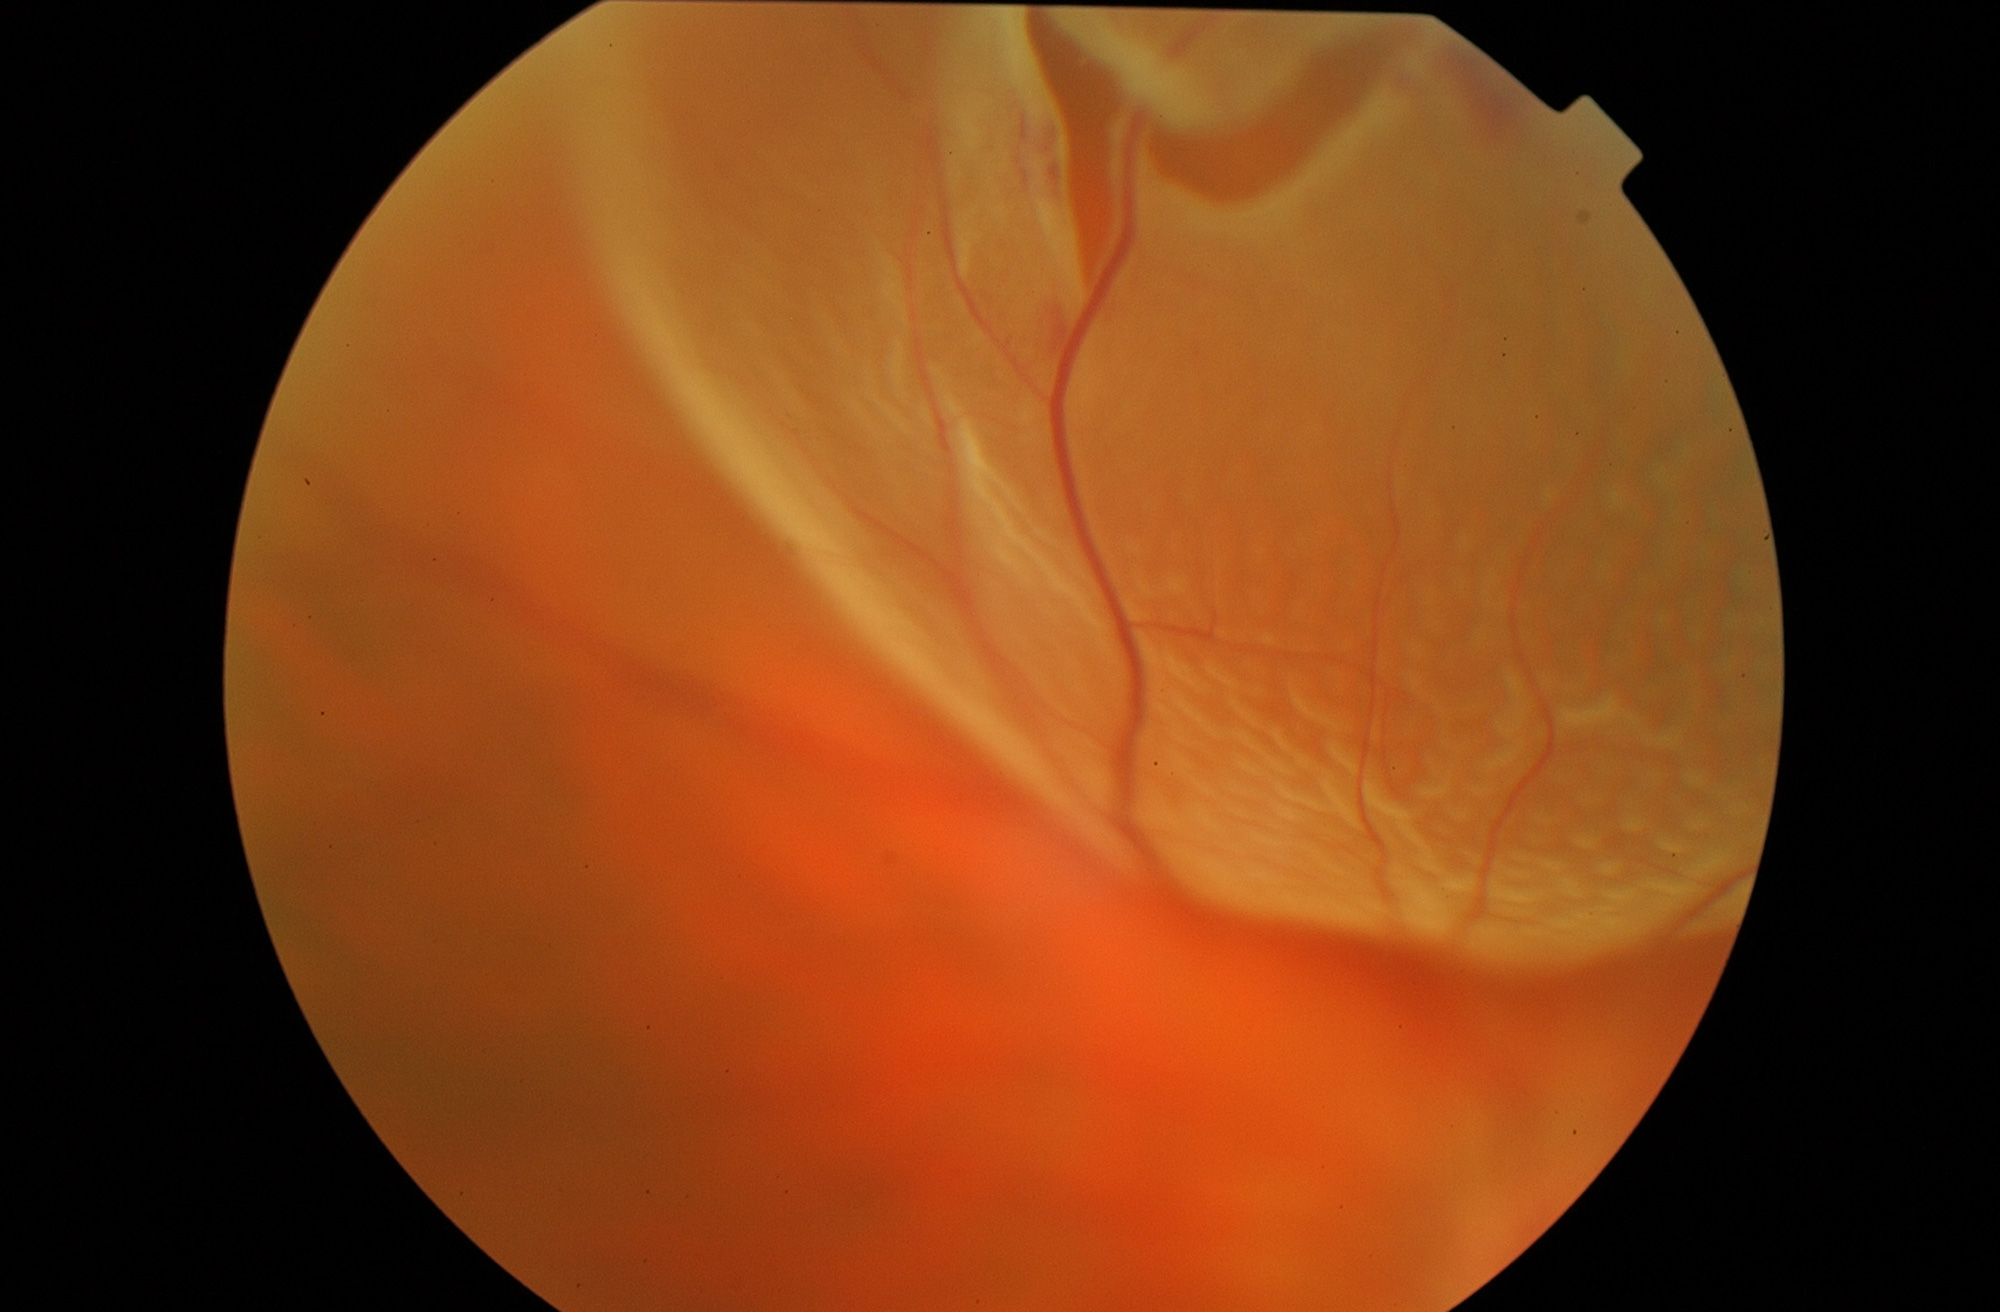

Desprendimiento de retina

El desprendimiento de retina consiste en la separación de la retina del resto de las capas externas del ojo, impidiendo su correcto funcionamiento y provocando una pérdida de visión.